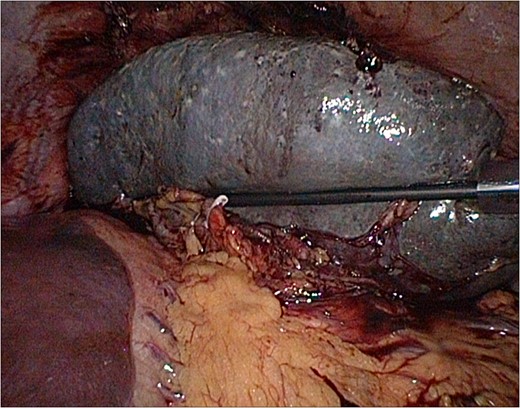

In January an uncomplicated laparoscopic splenectomy was performed. Intraoperatively, the enlarged spleen was completely covered in omentum and attached to the anterolateral abdominal wall by firm adhesions probably formed after the rupture (Figs 2 and 3). The postoperative course was complicated by a pneumonia for which antibiotics were prescribed. Patient recovered well and was discharged home within 1 week postoperative. Pathologic examination showed a substantially enlarged spleen of 855 g without any abnormalities.

Laparoscopy: spleen after dissection and clipping of the splenic artery.